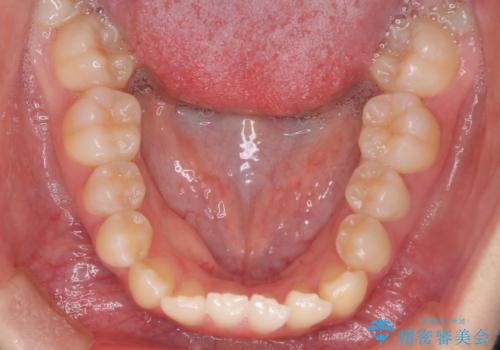

- 右上の小臼歯が大きくねじれており、噛み合わせや見た目に影響を与えている状態でした。診察の結果、インビザライン単独では十分な回転が得られにくいと判断。そのため、基本的な歯列の移動はインビザラインで行いながら、部分的にワイヤー矯正を併用するコンビネーション治療を計画しました。

まず、インビザラインで歯列全体を整えながら、スペースを確保しました。その後、部分ワイヤーを装着し、右上小臼歯の捻転を効率よく改善。ワイヤーの力を活用することで、より確実に歯の向きを整えることができました。治療後は、「しっかり噛めるようになり、見た目も自然になった」と患者様にもご満足いただきました。